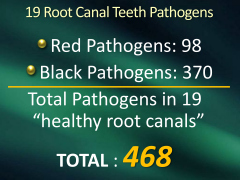

I dream that dentistry will finally discover

hundreds of microbes living under cover

Root canals have no MHC

so they become your enemy